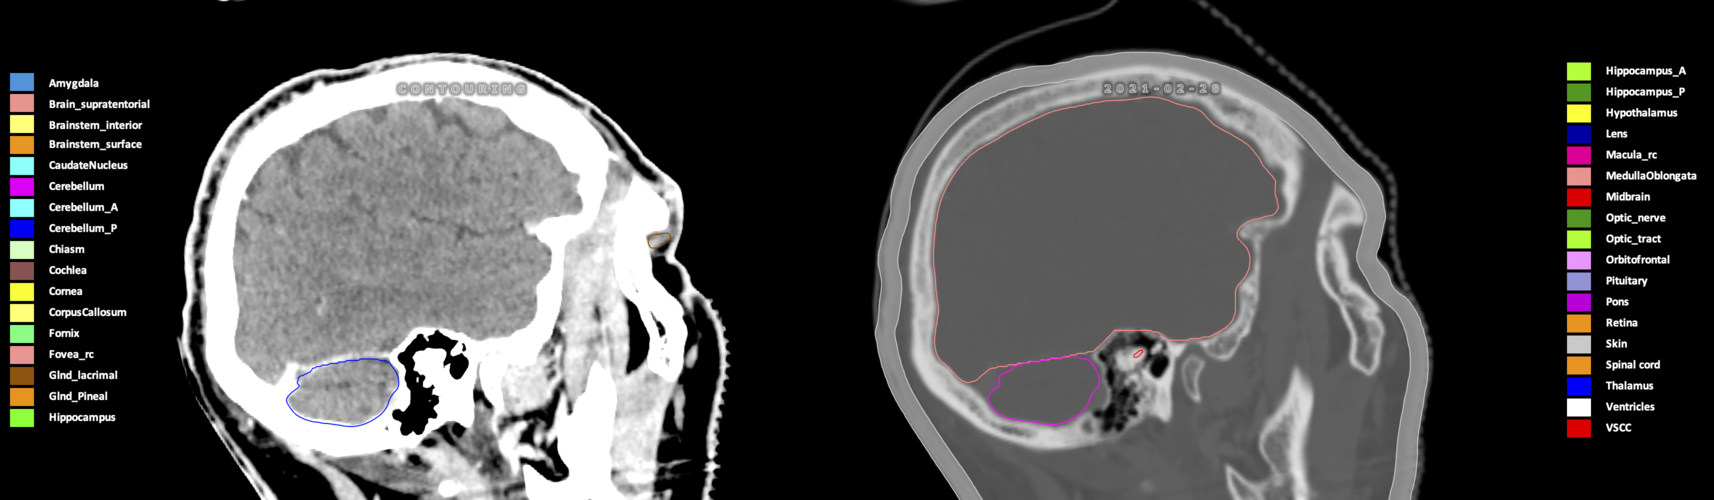

Three-dimensional delineation of the 25 consensus OARs for neuro-oncology are shown on CT (WW/WL 120/40, 3000/600), 3T MR images, (T1Gd, T2FLAIR 1mm) and 7T MR (MP2RAGE 0.7 mm). All are presented in transversal, sagittal and coronal view.

Included are all OARs known to be relevant for radiation-induced toxicity in neuro-oncology: brain, brainstem (midbrain, pons, medulla oblongata), chiasm, cerebellum (anterior & posterior), cochlea, cornea, hippocampus (anterior & posterior), hypothalamus, lens, lacrimal gland, optic nerve, pituitary, skin, and vestibular & semicircular canals. To further facilitate research on cognition, vision and radiological changes after irradiation of the brain, potential clinically-relevant OARs are included: amygdala, caudate nucleus, cerebellum (anterior & posterior), corpus callosum, fornix, macula, optic tract, orbitofrontal cortex, periventricular space (PVS), pineal gland, and thalamus.